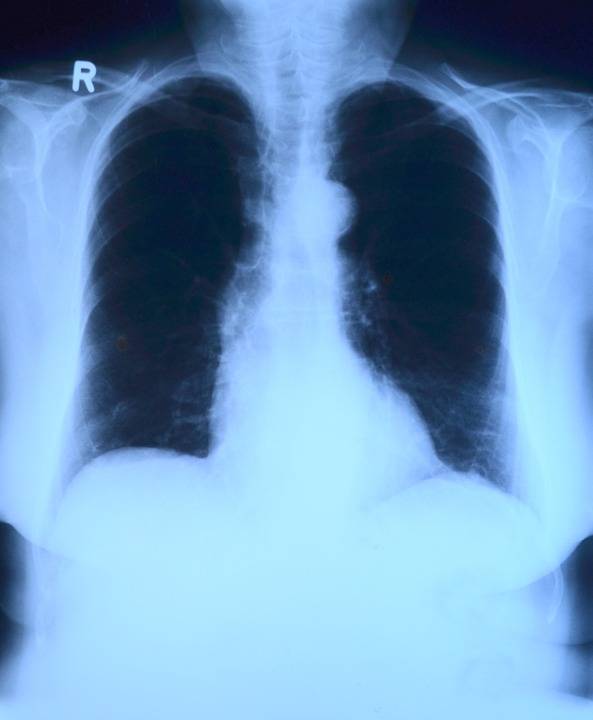

Polmoniti pneumococciche o da Klebsiella o da emofili Infiltrati diffusi possono essere osservati in. Essa viene frequentemente isolata in impianti di condizionamento e nellacqua potabile. Carinii polmonite da aspirazione TBC miliare sindrome da distress con polmonite. La polmonite da legionellosi colpisce persone di qualsiasi età ma gli uomini di mezza età sono più spesso malati.